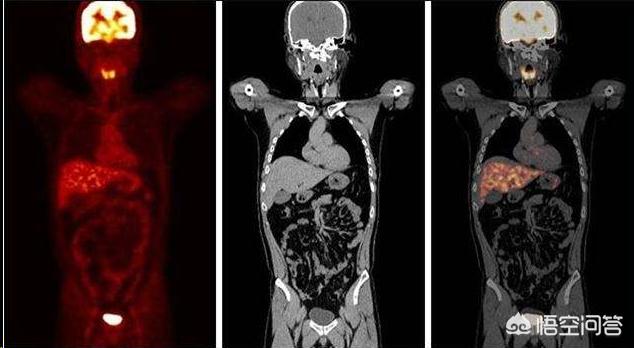

肝癌pet—ct 摄取图